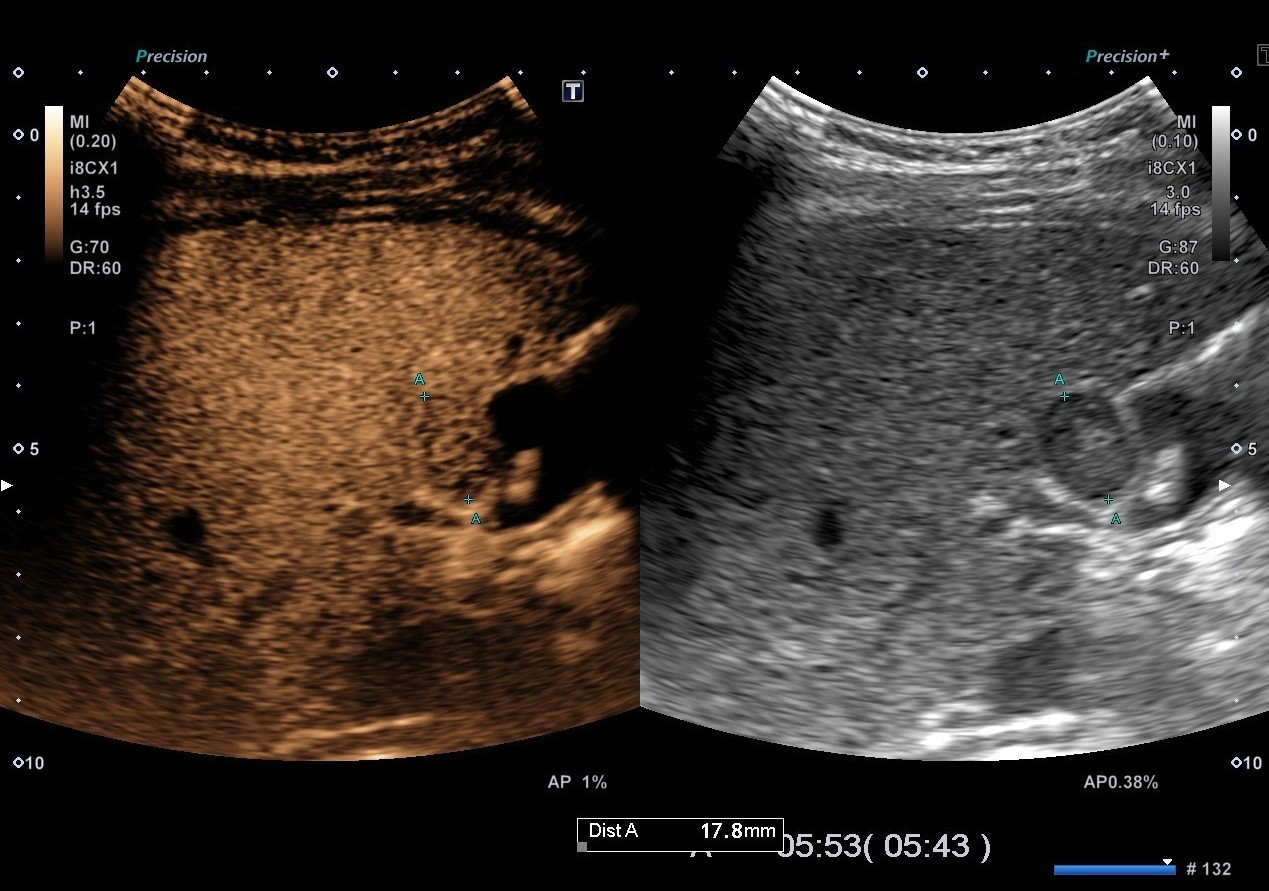

- 顯影劑注射後於超音波所呈現的影像變化